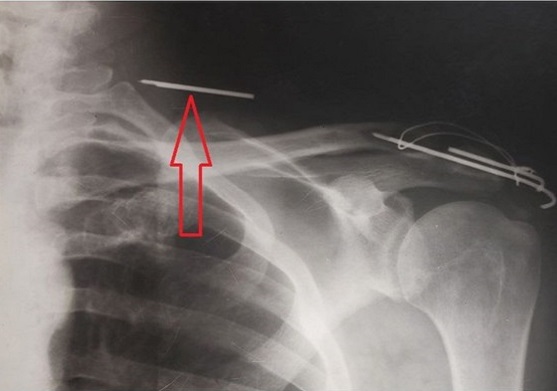

К специалистам ВГП обратился пациент, у которого был установлен остеосинтез ключичной кости и верхней части лопатки после перелома. Для восстановления стабильности и заживления поврежденных тканей в таких ситуациях врачи используют специальные имплантаты. Однако установленная спица после физической нагрузки сломалась. Отломившаяся часть проникла глубоко в мягкие ткани области шеи, где расположены жизненно важные органы.

Обломок врачи извлекли в малой операционной, которая располагается в кабинете хирурга. Спицу удалили, применив местную анестезию. Операцию успешно провели хирург, главный врач поликлиники №10 Евгений Копылов и ассистентка Алёна Игнатущенко.